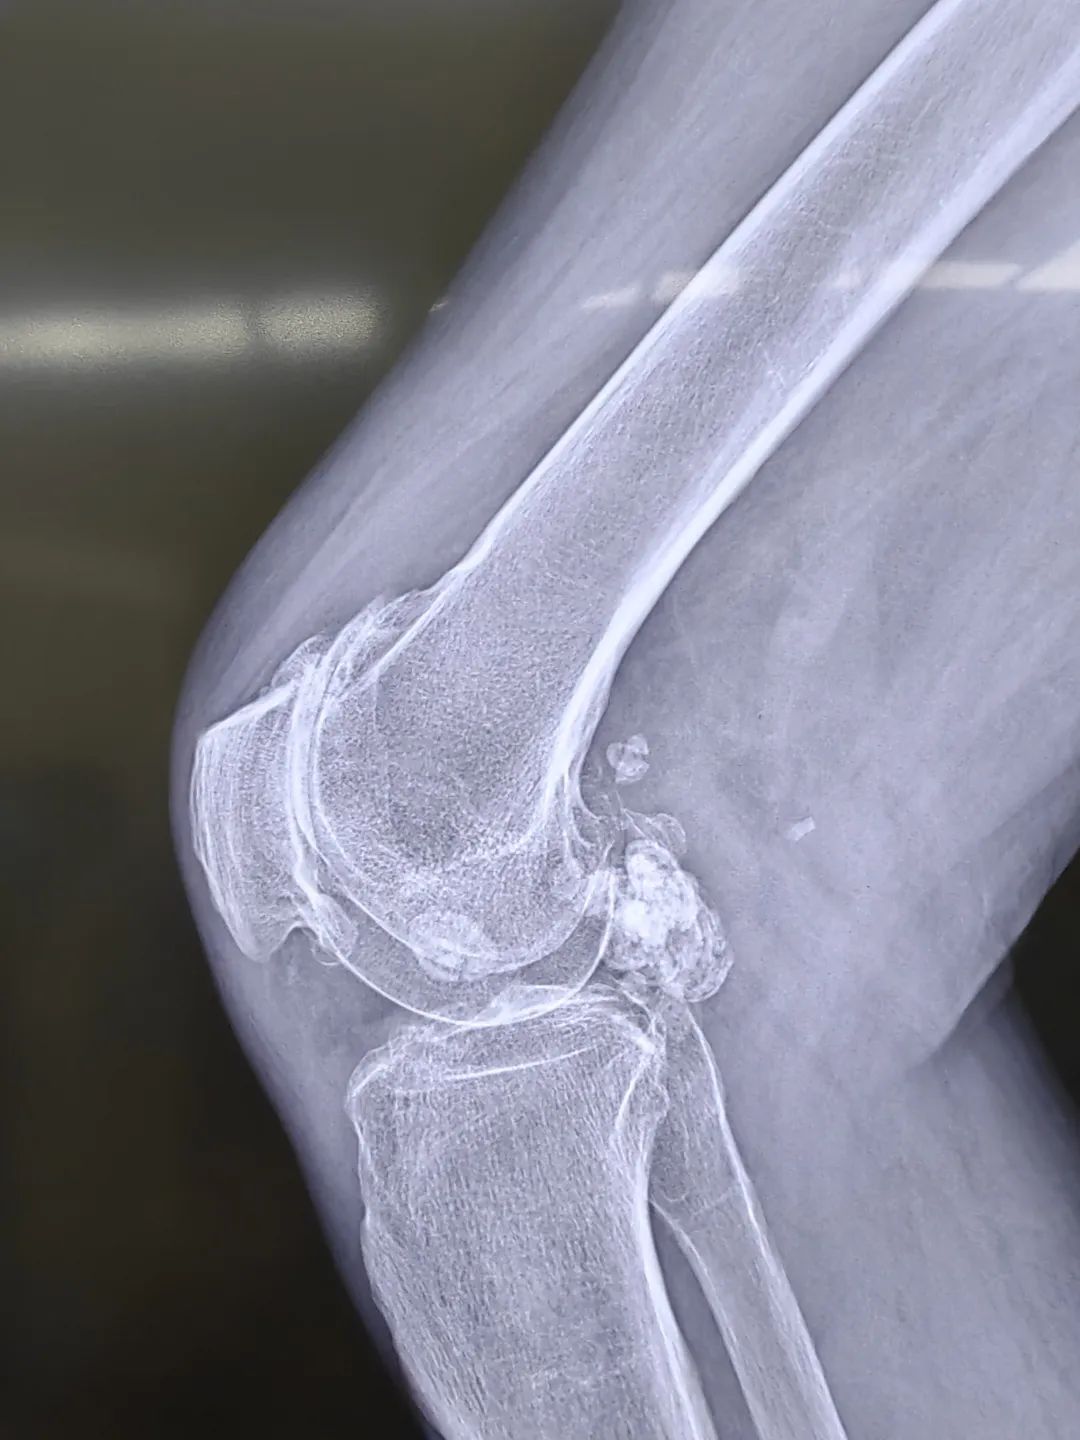

近日,我院骨科团队为一位78岁腘窝滑膜软骨瘤病女性患者进行了关节镜微创手术。由于病变位于腘窝,早期不影响膝关节活动,疼痛症状时轻时重,加上对开放手术的恐惧,患者竟然坚持了近40年,直到术前患者膝关节屈伸活动受限,患膝肿胀明显,因疼痛不敢负重走路,才下决心来院手术。

滑膜软骨瘤病病因不明确,好发于具有滑膜组织的关节囊或腱鞘内,多数学者认为滑膜软骨瘤病是一种滑膜化生性疾病,少数学者认为,该病变性质介于良性的内生软骨瘤与恶性的软骨肉瘤之间,滑膜软骨瘤病根据滑膜化生学说分为原发型和继发型两大类;原发型指的是以胚胎学说为主,即残存胚胎组织活化、增生,引起滑膜化生。继发型指的是炎症、外伤等因素刺激关节滑膜化生引起关节内游离体形成。滑膜骨软骨瘤病进展形成游离体后,会引起关节绞索,疼痛等症状,这时就需要进行手术干预,以减轻对关节的进一步损伤,改善患者的生活质量。

近年来,随着膝关节镜技术的发展,膝关节后室以及腘窝等处疾病的关节镜技术日趋成熟,比如后交叉韧带止点撕脱骨折、腘窝囊肿、膝关节后室游离体等疾病逐渐由传统开放手术转为微创关节镜手术。由于腘窝含有国动静脉、胫腓神经等重要结构,对于该处关节镜手术需要有非常熟练得关节镜基础,和一定的学习曲线。